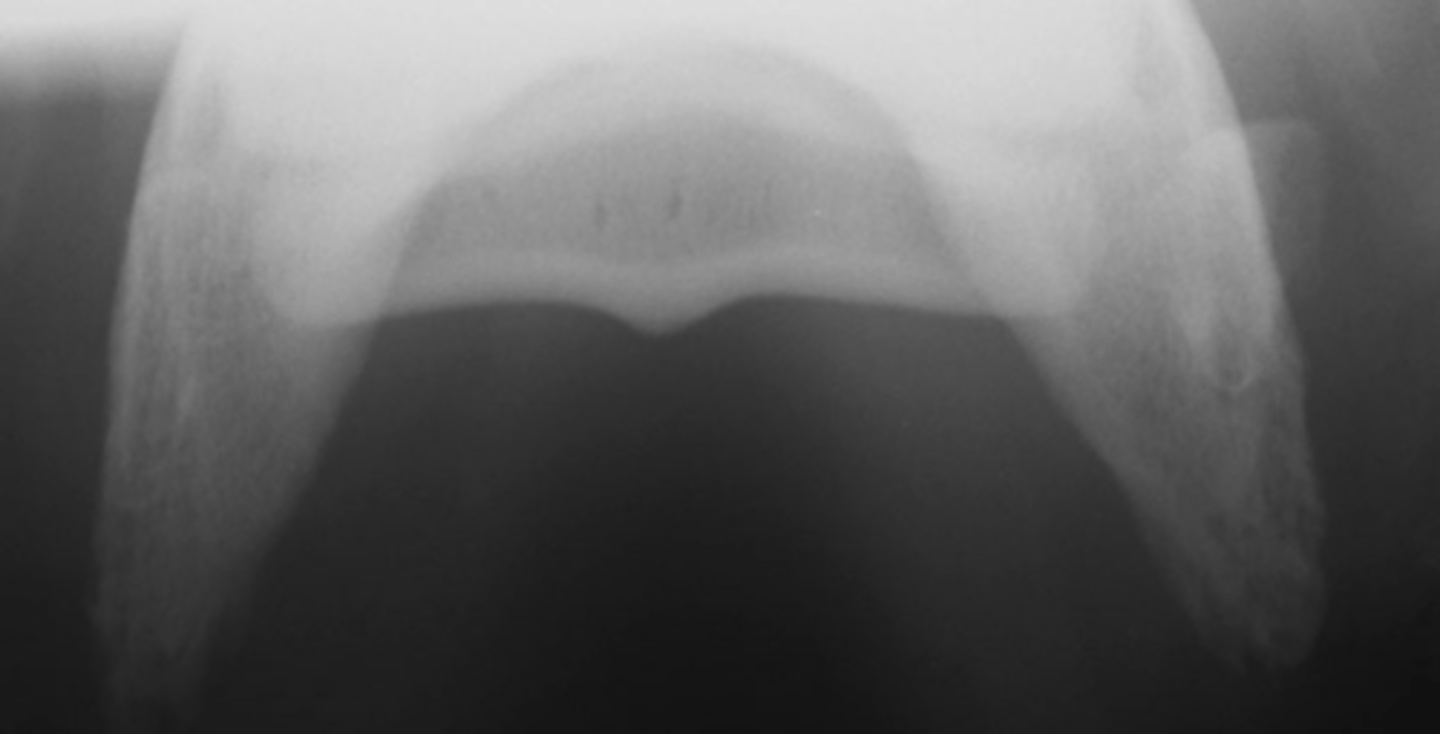

Flexor skyline

What view is this?